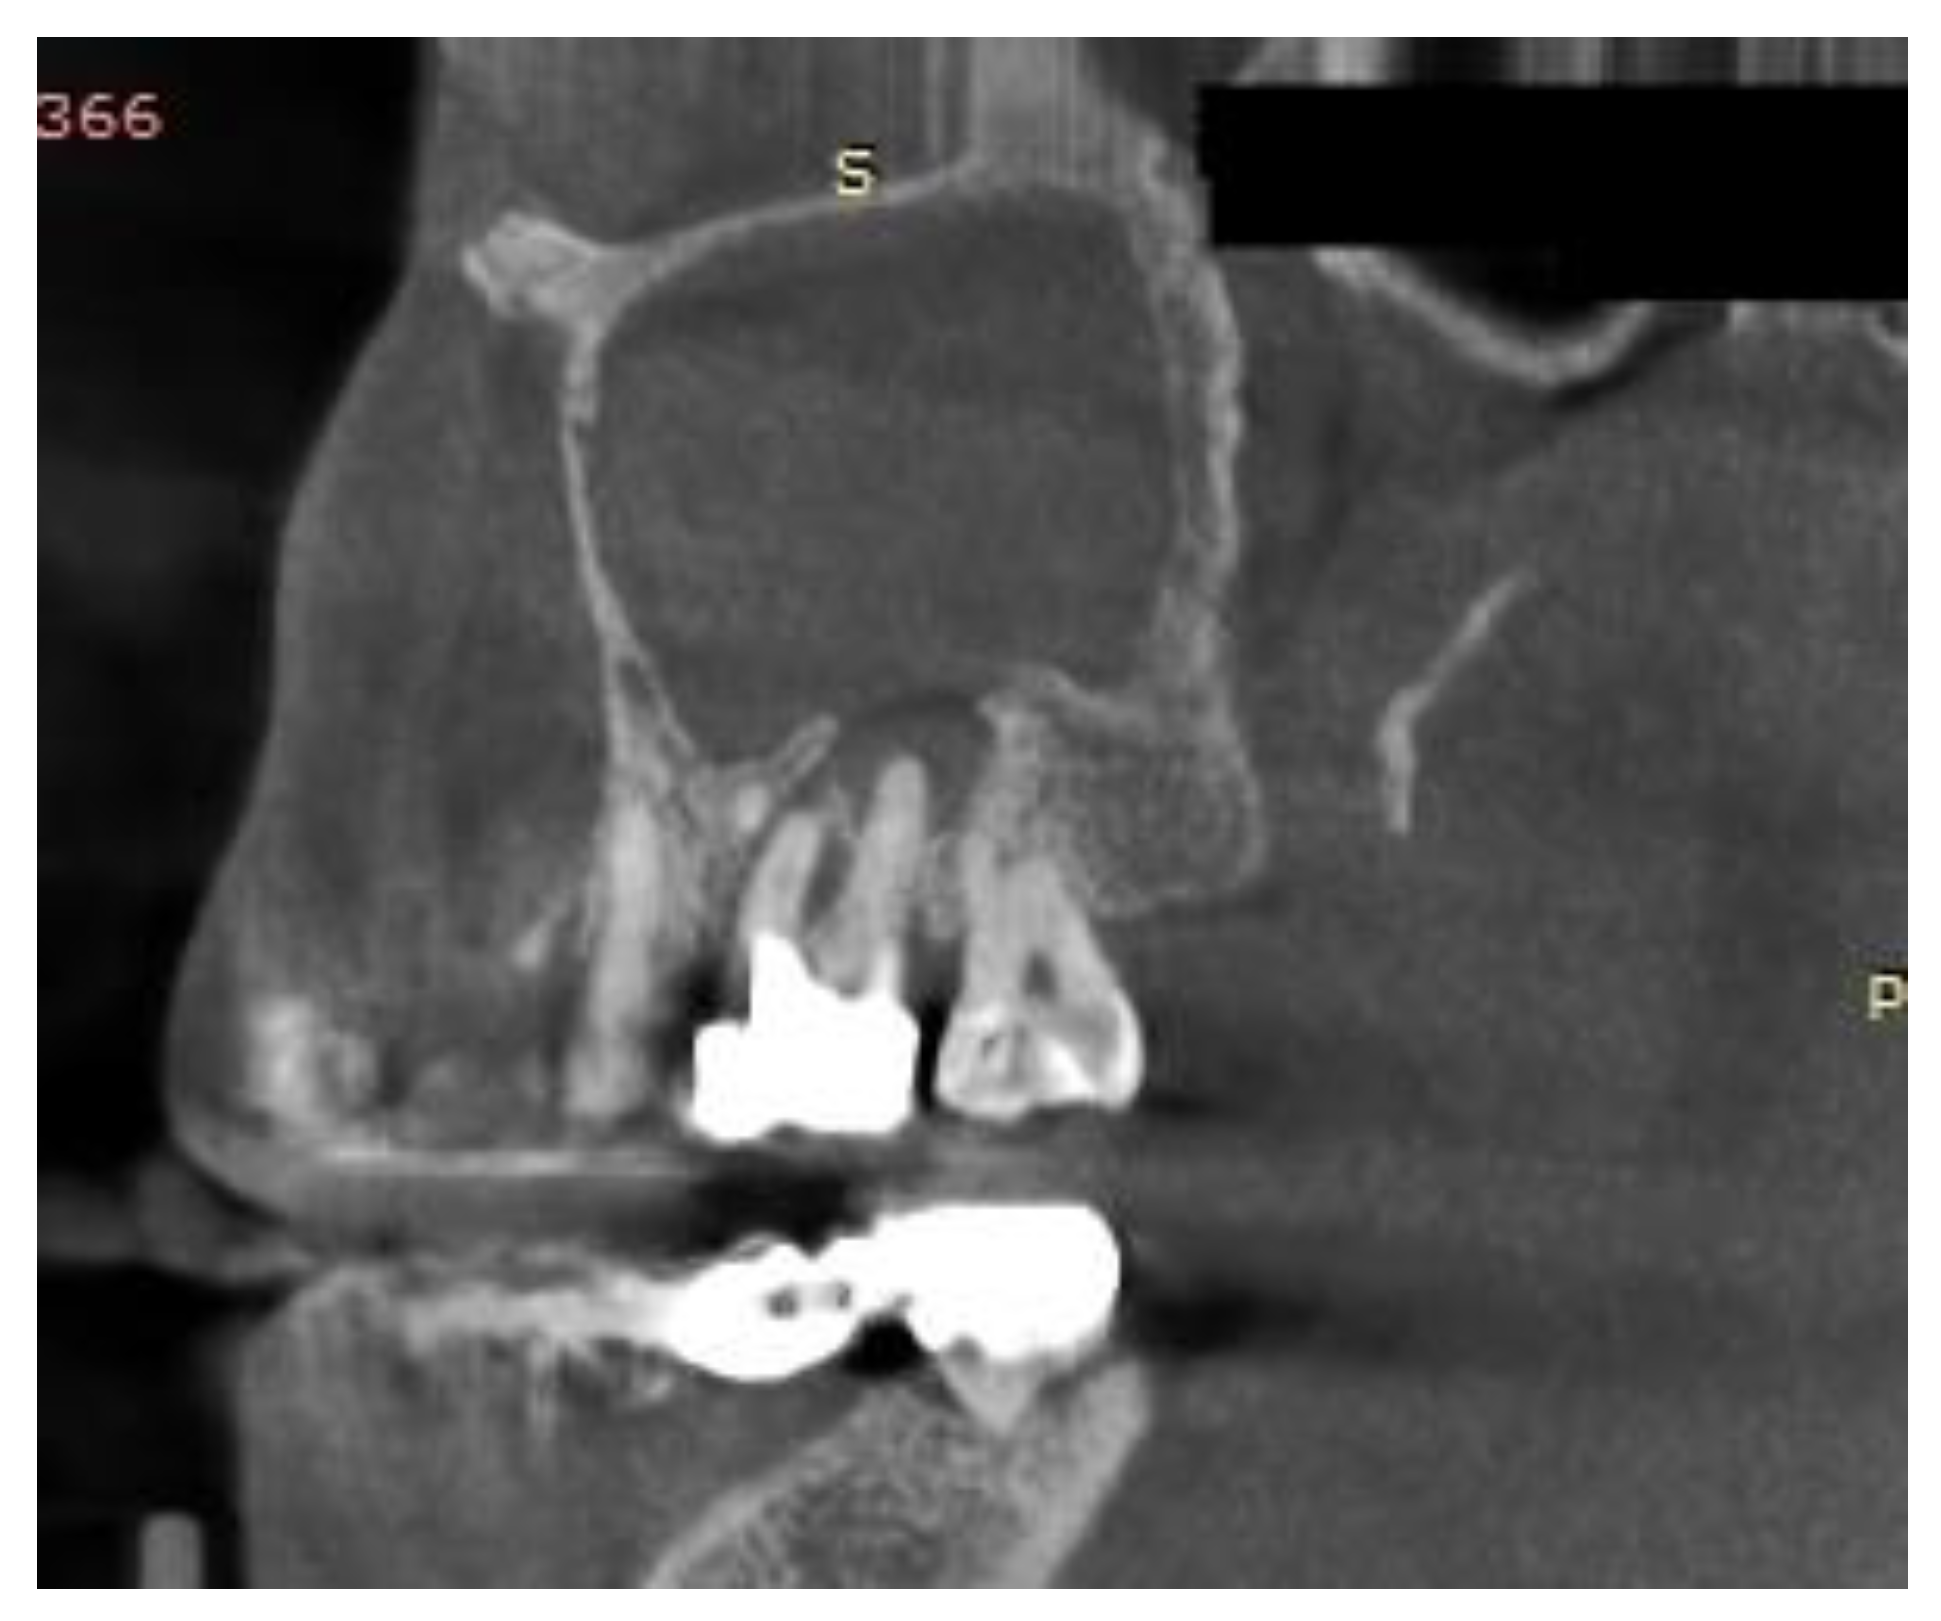

Figure 4.

Sagittal CBCT of a patient with odontogenic sinusitis caused by a periapical abscess.